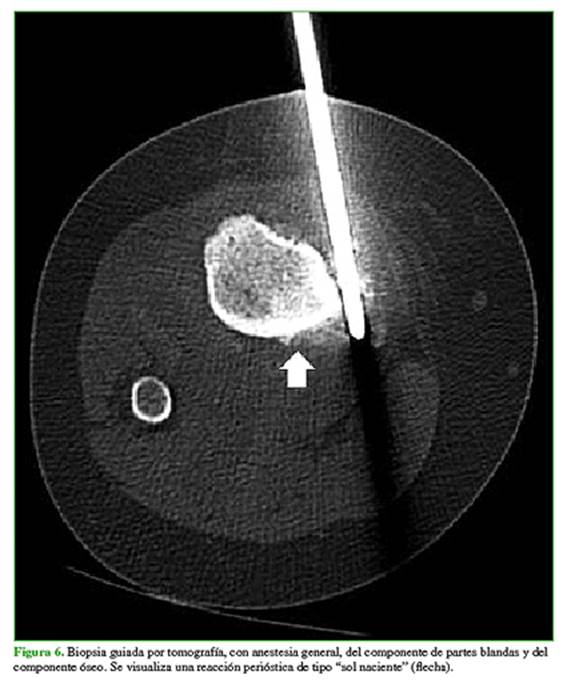

Se plantea una biopsia guiada por tomografía (Figura 6), con anestesia general.

Permiten definir mejor la matriz osteoide, pero el estudio solo se destina para la toma de biopsia. Se puede visualizar necrosis en las masas de partes blandas con zona de baja atenuación.

Biopsia guiada por imágenes

Se debe planificar junto con especialistas en estudios por imágenes y el cirujano oncológico. Hay que atravesar solo un compartimento y recordar que el trayecto de la aguja debe ser resecado.